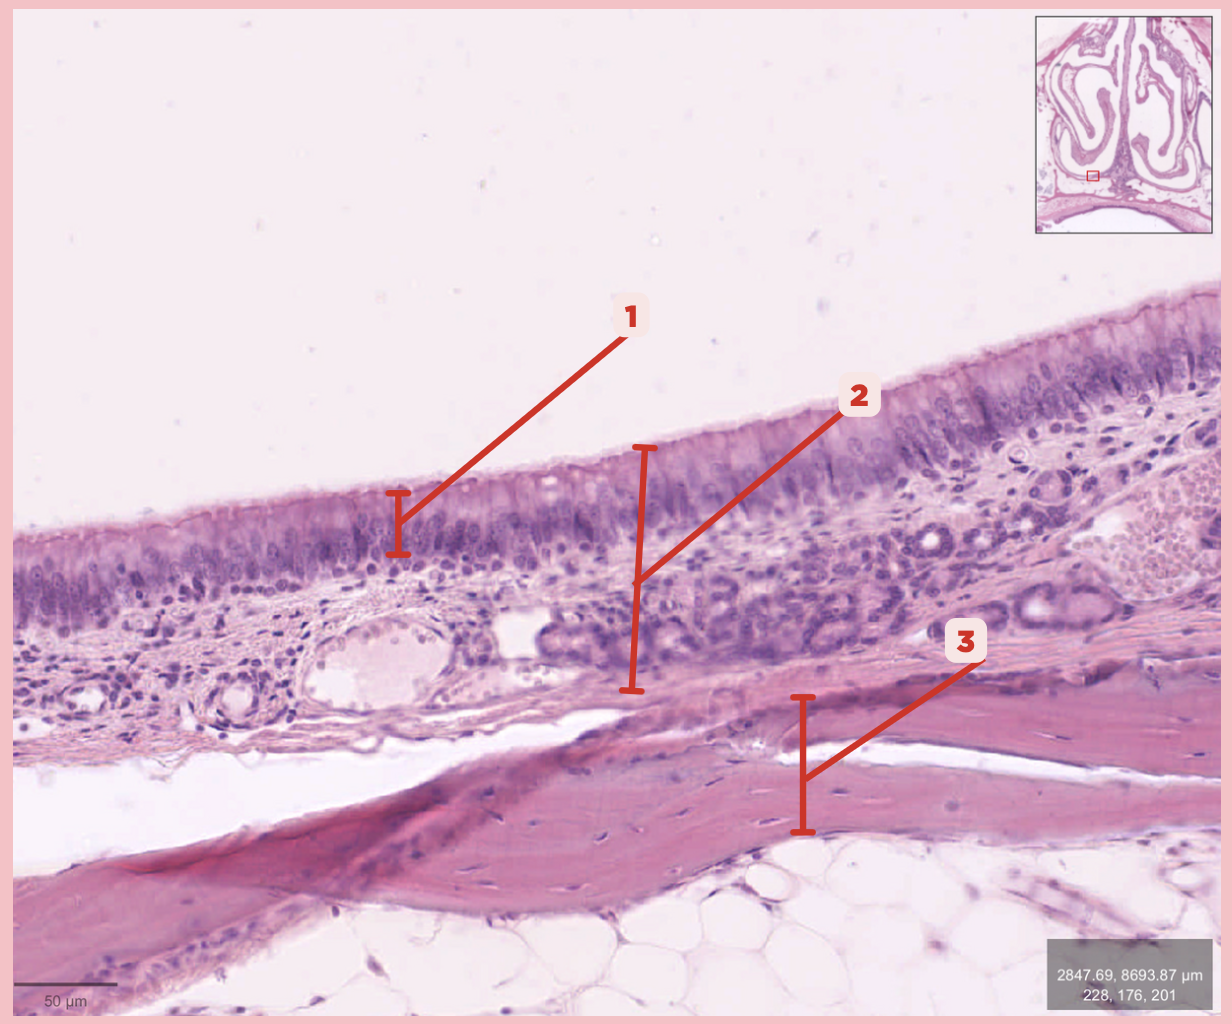

Respiratory Epithelium

Identify the structure labeled as 1.

Lamina Propria

Identify the structure labeled as 2.

Bony spicule

Identify the structure labeled as 3.

Respiratory Epithelium

Identify the structure labeled as 1.

Mucosa

Identify the structure labeled as 2.

Bone

Identify the structure labeled as 3.

Keratinized stratified squamous epithelium

What’s the lining epithelium at #3?

No

Are Glands present at #1?

Lamina Propria

Identify the structure labeled as 1.

Adipocytes

Identify the structure labeled as 2.

Keratinized stratified squamous epithelium

Identify the structure labeled as 3.